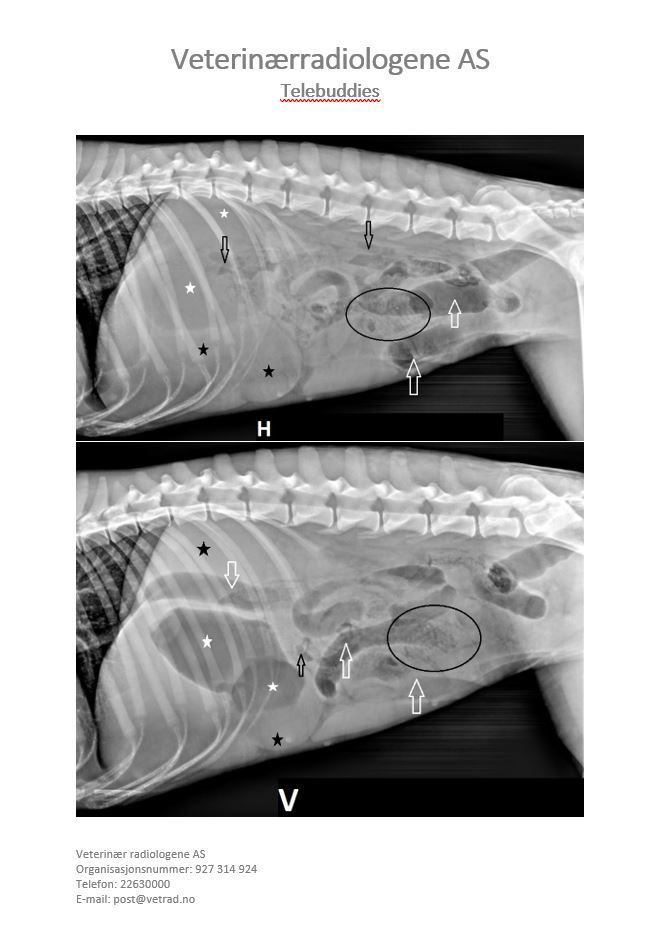

Signalement: Dachs, tispe, 11 år Anamnese: Mistanke magedreining